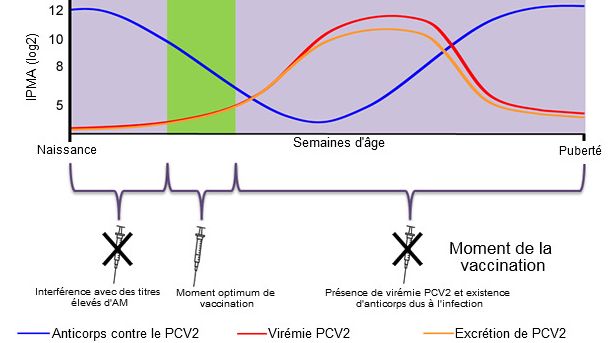

Cet article explique les facteurs à prendre en compte pour déterminer le moment optimum de la vaccination contre le PCV2 et montre les résultats d'une étude qui mesure l'efficacité de différents programmes vaccinaux dans un élevage avec une infection subclinique.

La façon la plus efficace d'éviter des pertes productives associées au PCV2 est d'éviter que la virémie se produise en indusant une immunité passive ou active qui minimise la circulation du virus dans l'élevage.